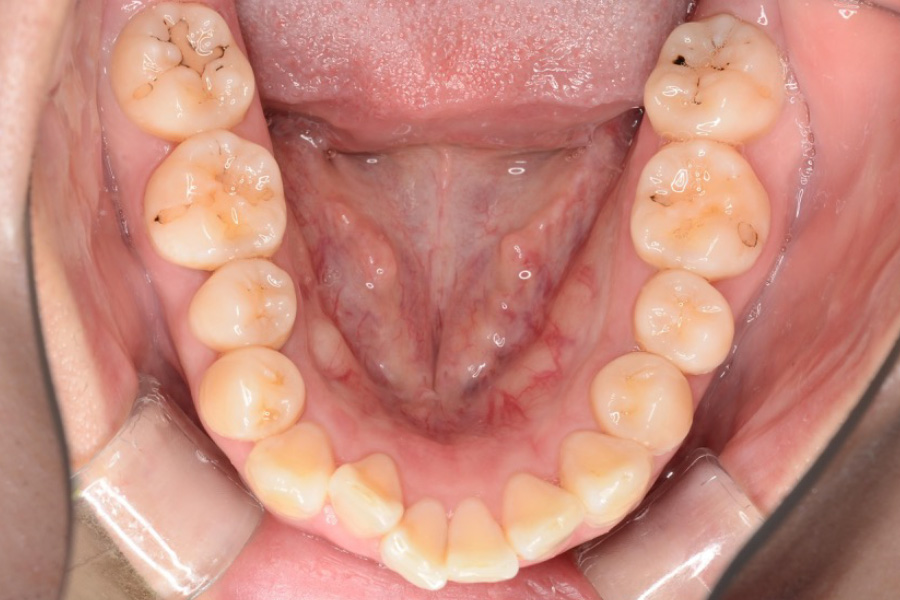

治療前

主訴 歯のガタつき

治療内容 インビザライン矯正

小臼歯抜歯